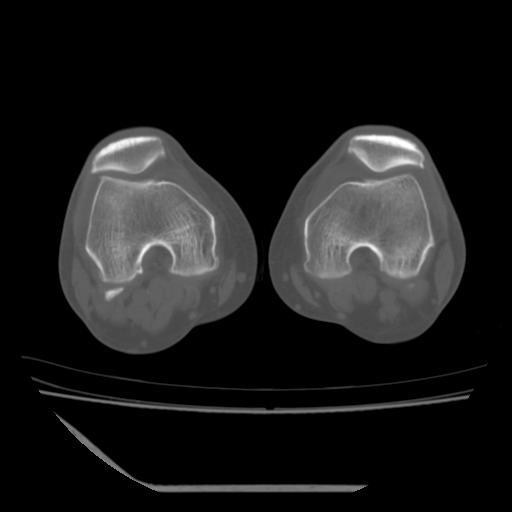

标题: CT13225:老年男性,左膝关节疼痛数月;请各位老师讨论。 [打印本页]

标题: CT13225:老年男性,左膝关节疼痛数月;请各位老师讨论。

骨质增生,骨性关节面硬化,关节积液,考虑退行性骨关节病

关节腔内少量积液,关节面退变。

双膝退变

骨质增生,骨性关节面硬化,关节间隙失常,关节积液,考虑退行性骨关节病.

这个病例诊断:退行性骨关节炎